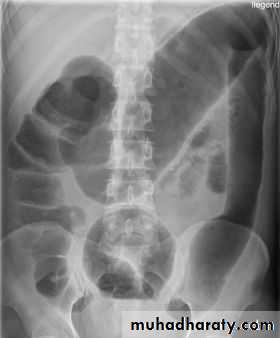

Causes of bowel dilatation

• Mechanical SB obstruction : small bowel dilation with normal or reduced caliber of colon• Mechanical LB obstruction: dilated colon down to the point of obstruction. May be accompanied by small bowel dilation if the ileocecal valve becomes incompetent

• Generalized paralytic ileus: SB and LB dilatation, gas may be present in the rectum

• Localized peritonitis: dilatation of loops adjacent to inflammatory process (sentinel loops)

• SB infarction : mimic obstruction of SB or LB depending on distribution of ischemia

• Closed loop obstruction : e.g. cecal and sigmoid volvulus

• Toxic dilatation of the colon: the dilatation is maximal in transverse colon more than 6 cm The haustra are lost or grossly abnormal . Ulcerative colitis is the commonest cause